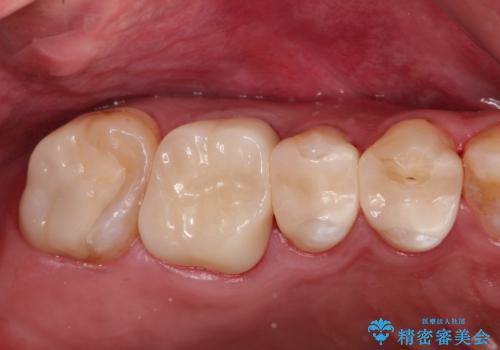

金属だらけの奥歯 根管治療のやり直しとセラミック化

金属の奥歯 → 白い奥歯 根管治療からのやり直し